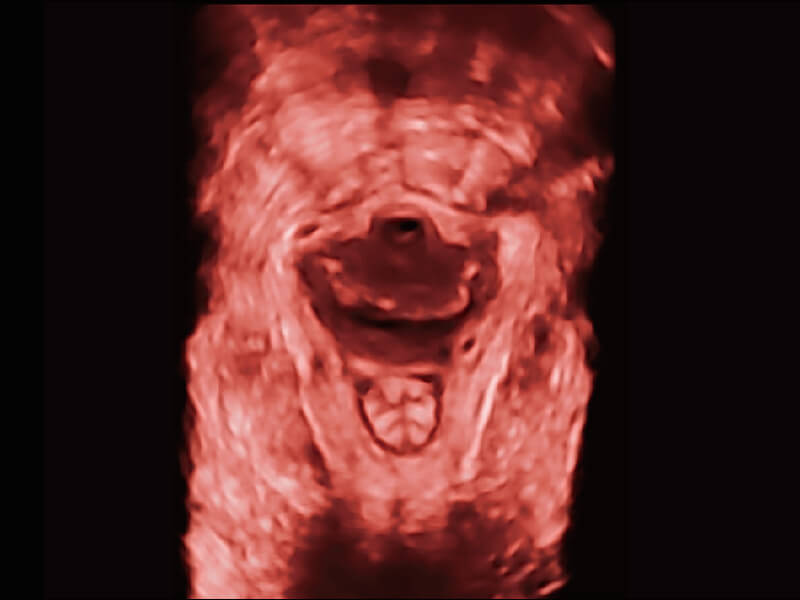

高分辨率容积成像 栩栩如生

超宽频带技术,为容积成像带来优质的二维图像基础,为您呈现丰富的结构细节,栩栩如生地展示宝宝的宫内形态以及各种组织的立体结构。

• 高分辨率容积探头( VC2-9A )

临床图